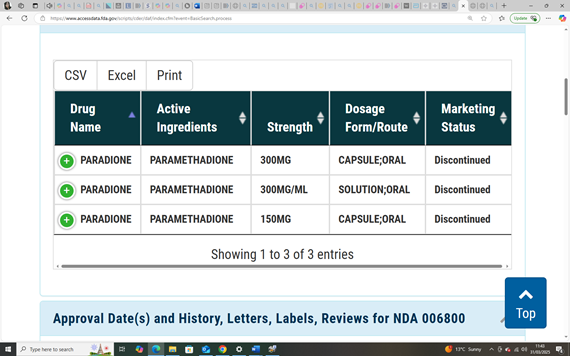

In 1949, the FDA had already approved a different drug: paramethadione, a structural analogue of trimethadione, both part of the oxazolidinedione class of anticonvulsants. Marketed under the name Paradione by Abbott Laboratories, paramethadione was prescribed in the U.S. for absence seizures (NCATS).

Paramethadione (marketed as Paradione by Abbott Laboratories) was distributed in the United States and Canada, where it was prescribed for absence seizures throughout the 1950s and 1960s (CMAJ, 1959; PDR, 1954). To date, aside from Canada, no verified evidence of its approval or distribution has been found in thalidomide-affected regions such as the UK, Australia, or Germany, supporting the theory that paramethadione did not appear in those markets.

Paramethadione: A teratogen quietly removed in Canada after its official last FDA order in 1989, making it impossible to attribute outcome shifts to known regulatory action (FDA, N.D). (See Report Section 12 – Foundational Studies).